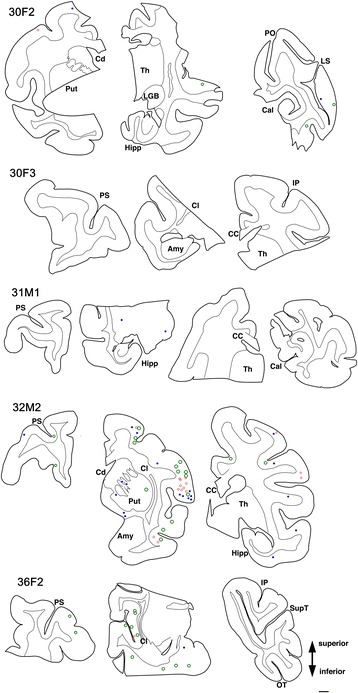

Tau-positive lesions were particularly numerous in the oldest monkey examined (36 yo Fig. 1). However, these cytopathological findings, including pretangle forms of tau in neurons, tau-positive astrocytes, and inclusions in oligodendroglia-like cells, were also detected in brain sections from other monkeys older than 30 years of age (Fig. 5). Similar to the 36-year old monkey, tau-positive lesions were seen more frequently in the neocortex than in the hippocampus (Fig. 5).

In all brains examined in this study, tau-positive structures exhibited immunoreactivity for 4R, but not 3R tau. Tau-positive structures were also argyrophilic with Gallyas, but not with Campbell-Switzer silver impregnation. This cytopathology is different from that of AD, which usually exhibits immunoreactivity for both 3R and 4R tau, and argyrophilia with both Gallyas and Campbell-Switzer silver impregnations [ref. 19]. Instead, these phenotypes suggest that a PSP or CBD-like cytopathology may occur in brains of aged primates. Supporting this idea, the 4R-positive structures that we identified around blood vessel in old primates (Fig. 3b) are similar to tau-positive structures identified in tuft-shaped astrocytes in PSP and astrocytic plaques in CBD [ref. 25]. Further, we did not observe tau IR in neurites around senile plaques (Fig. 3a, asterisk), suggesting that most tau-positive structures in old primate brains may be of glial origin similar to human PSP/CBD, which are not frequent in aged human brains with AD pathologies. Moreover, these tau-positive astrocytes are morphologically different from thorn-shaped astrocytes, granular/fuzzy astrocytes grouped under the umbrella of “aging-related tau astrogliopathy [ref. 22]” Consistent with our results, Kiatipattanasakul and colleagues [ref. 26] previously described PSP-like tau deposition in neurons and glia in an aged (35 yo) albino cynomolgus monkey. They also observed Gallyas-positive glia in the basal ganglia, thalamus, brainstem and the white matter as well as NFTs in the thalamus. However, they proposed that the occurrence of PSP-like cytopathology in their monkey brain was exceptional. In our study, however, we observed similar neuronal and glial cytopathological alterations of tau in 5 out of 7 monkeys over 30 years of age (Table 2, Fig. 5), suggesting that PSP-like cytopathologies may instead represent a common aspect of aged monkey brains.

PSP-like distribution of tau cytopathologies in aged monkey brains

Although tau-positive lesions were found in temporal and hippocampal areas in the oldest monkey examined (36 M, Fig. 1), lesions were also abundant in the white matter and basal ganglia, predominantly in oligodendroglia-like cells and as intrafascicular threads. In other monkeys over 30 years of age, lesions were present in the frontal and temporal neocortices and basal ganglia rather than in the hippocampus (Fig. 5). Again, this distribution of tau-positive lesions is reminiscent of the aged cynomolgus monkey described by Kiatipattanasakul et al. [ref. 26], and suggest cytopathological alterations characteristic of PSP rather than those of AD [ref. 10, ref. 13]. A similar cortical distribution of tau lesions, different from human AD, has been reported in the brains of gorilla [ref. 14, ref. 15]. Taken together, tau-positive lesions in aged non-human primate brains do not necessarily represent AD-like pathogenesis even though Aβ deposits may be present in the same specimens.